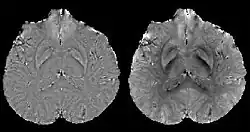

Estimated local field maps using left) high-pass filtering method, right) projection onto dipole fields (PDF) method.

In human brain quantitative susceptibility mapping, only the local susceptibility sources inside the brain are of interest. However, the magnetic field induced by the local sources is inevitably contaminated by the field induced by other sources such as main field inhomogeneity (imperfect shimming) and the air-tissue interface, whose susceptibility difference is orders of magnitudes stronger than that of the local sources. Therefore, the non-biological background field needs to be removed for clear visualization on phase images and precise quantification on QSM.

Ideally, the background field can be directly measured with a separate reference scan, where the sample of interest is replaced by a uniform phantom with the same shape while keeping the scanner shimming identical. However, for clinical application, such an approach is impossible and post-processing based methods are preferred. Traditional heuristic methods, including high-pass filtering, are useful for the background field removal, although they also tamper with the local field and degrade the quantitative accuracy.

More recent background field removal methods directly or indirectly exploit the fact that the background field is a harmonic function. Two recent methods based on physical principles, projection onto dipole fields (PDF)[8] and sophisticated harmonic artifact reduction on phase data (SHARP),[9] demonstrated improved contrast and higher precision on the estimated local field. Both methods model the background field as a magnetic field generated by an unknown background susceptibility distribution, and differentiate it from the local field using either the approximate orthogonality or the harmonic property. The background field can also be directly computed by solving the Laplace's equation with simplified boundary values, as demonstrated in the Laplacian boundary value (LBV) method.[10]